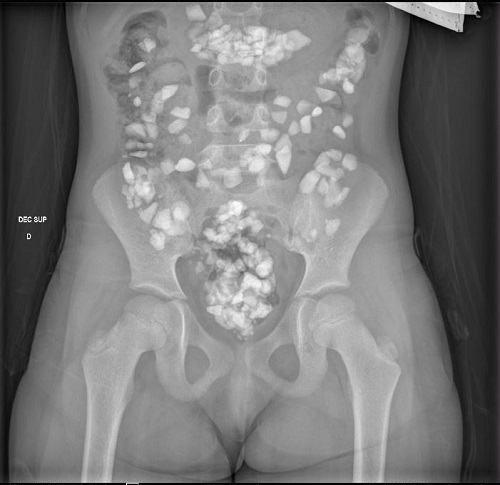

Presentamos a una paciente de seis años cuya madre consulta por observar piedras en las heces de la niña. Relata un episodio similar hace 48 horas, hallando en dicha ocasión restos de cuerda. La paciente admite dicha ingesta, sin explicar motivación alguna y presenta una leve gastralgia. A la exploración presenta un triángulo de evaluación pediátrica estable con constantes normales. Coloración de piel y mucosas normal y resto de la exploración física anodina. Se solicita radiografía de abdomen en la que se observan múltiples cuerpos extraños radioopacos, sin signos de obstrucción (Fig. 1). Se solicita, por tanto, estudio analítico destacando anemia ferropénica (hemoglobina de 9,5 g/dl, hematocrito de 31,6%, volumen corpuscular medio de 64,4 fl, ADE de 18,1%, hierro 12 µg/dl) e hipovitaminosis D (6,54 µg/l). Se inicia tratamiento con hierro oral y vitamina D, se indican modificaciones dietéticas y se realizan controles clínico-analíticos seriados presentando normalización de los parámetros analíticos y mejoría clínica evidente.

| Figura 1. Radiografía de abdomen. Se observan múltiples cuerpos extraños radioopacos (piedras), sin signos de obstrucción intestinal |